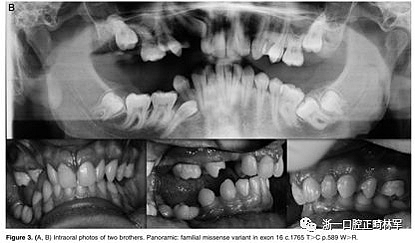

最后,在數(shù)據(jù)庫(kù)中以前沒有報(bào)道的錯(cuò)義變體在外顯子16 c.1765 T>C p.Trp89Arg中發(fā)現(xiàn)。 在同一家庭的三個(gè)成員 - 母親,女兒和兒子(圖3A,B)中發(fā)現(xiàn)的錯(cuò)義變體-負(fù)責(zé)用精氨酸p:Trp89Arg取代氨基酸色氨酸,這是一種具有不同化學(xué)特性的氨基酸。該突變發(fā)生在PTH1R蛋白質(zhì)的胞質(zhì)結(jié)構(gòu)域中,并參與受體與激活細(xì)胞內(nèi)級(jí)聯(lián)信號(hào)的G蛋白的相互作用。此外,計(jì)算機(jī)結(jié)果表明,PTH1R蛋白質(zhì)中的這種氨基酸取代改變了蛋白質(zhì)的結(jié)構(gòu)和功能,因?yàn)樗l(fā)生在蛋白質(zhì)的催化結(jié)構(gòu)域內(nèi)。

圖3.(A,B)兩兄弟的口內(nèi)照片。全景:外顯子16中的家族錯(cuò)義變體c.1765 T>C p.589 W>R

屬于2號(hào)家庭的小女兒(2:2)表現(xiàn)出更復(fù)雜的臨床表現(xiàn),缺乏永久性以及暫時(shí)性系列和囊性結(jié)構(gòu)元素的萌出(圖3A,B)。在哥哥(II:1;圖3A,B)中發(fā)現(xiàn)由于包括多顆恒牙的嚴(yán)重的雙側(cè)后牙開合。最后,患者II:1和II:2的母親表現(xiàn)出雙側(cè)上頜第一磨牙和下磨牙的包埋。發(fā)現(xiàn)前磨牙層面沒有咬合接觸(圖3A,B)。